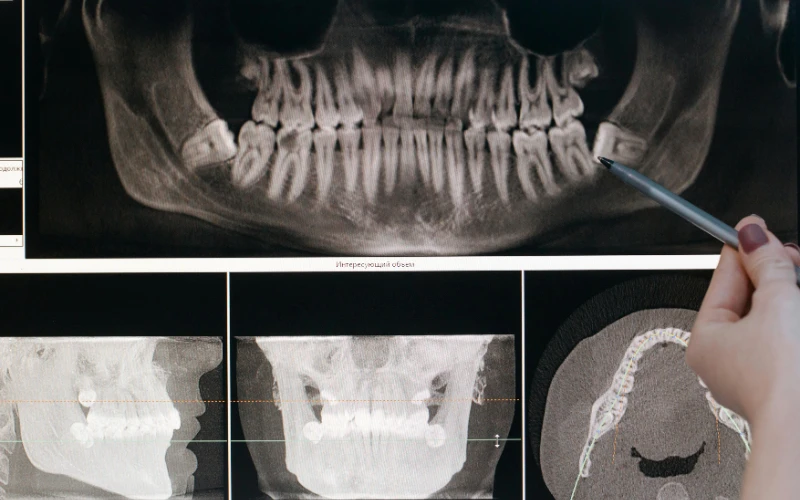

How Early Can X-Rays Detect Wisdom Teeth Growth?

Wisdom teeth development can be identified by dental X-rays at the age of 10–12. A panoramic X-ray may show wisdom tooth buds at this stage.

X-rays are critical tools for assessing the presence, placement, and development of wisdom teeth. To check tooth growth and angulation, dentists suggest panoramic or periapical X-rays. These images let dentists assess wisdom tooth size, position, and orientation before they emerge.